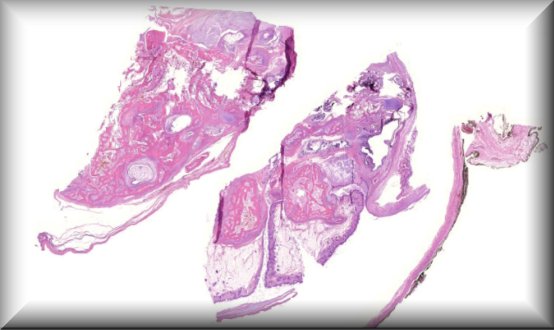

Cristina Peris Martínez (Guest): Histological findings after corneal ring segments explantation in a patient with radial keratotomy and post-LASIK ectasia. |